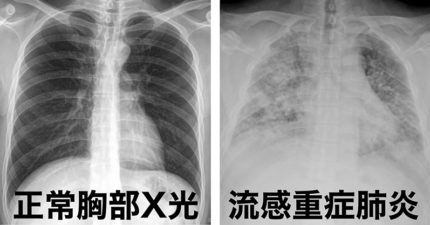

怎麼肺炎人就走了?胸腔醫示警6症狀快送醫「死亡率高達40%」

大S猝逝!醫曝「恐怖缺氧」真相 這徵兆恐24小時喪命

大S病逝「死於重症大白肺」 醫白話解釋:被痰活活淹死

大S被指「血氧降到89%」 醫驚喊:只能撐幾小時